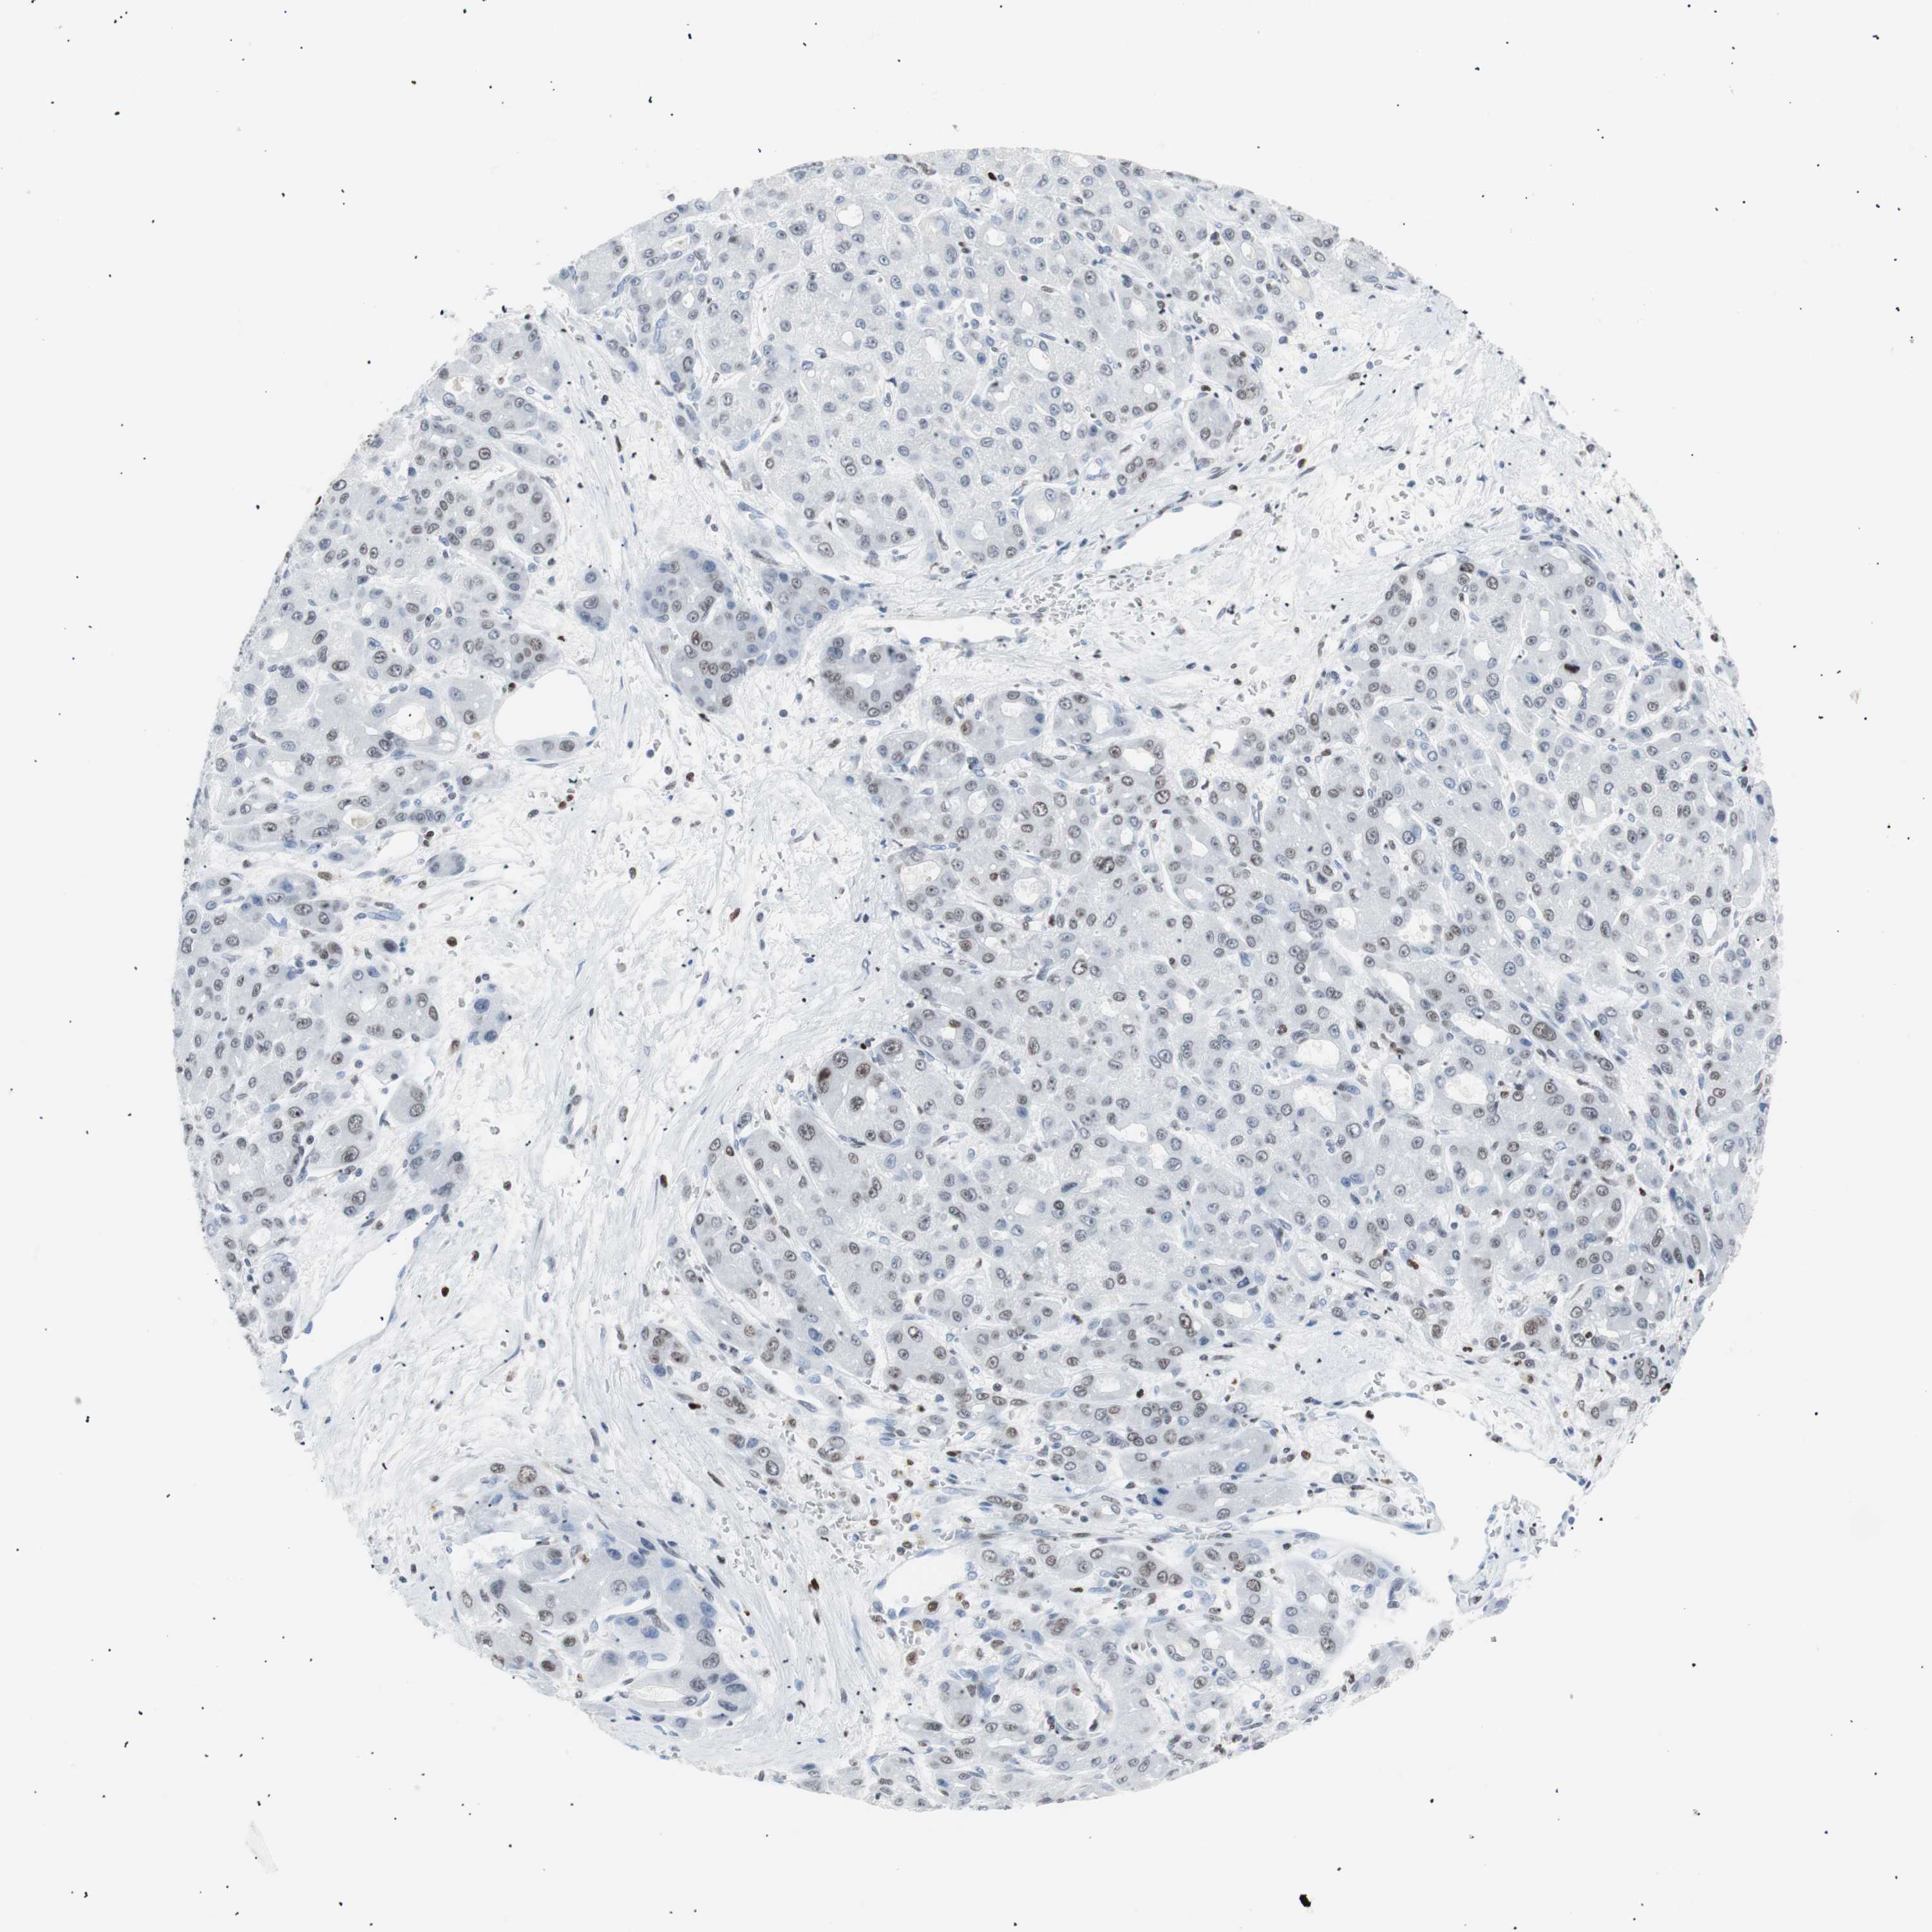

LIVER CANCER - Protein expressioni

A mouse-over function shows sample information and annotation data. Click on an image to view it in a full screen mode. Samples can be filtered based on level of antibody staining by selecting one or several of the following categories: high, medium, low and not detected. The assay and annotation is described here.

Note that samples used for immunohistochemistry by the Human Protein Atlas do not correspond to samples in the TCGA dataset.

Antibody stainingi

Antibody staining in the annotated cell types in the current human tissue is reported as not detected, low, medium, or high, based on conventional immunohistochemistry profiling in selected tissues. This score is based on the combination of the staining intensity and fraction of stained cells.

Each image is clickable and will lead to virtual microscopy that enables deeper exploration of all samples and also displays staining intensity scores, fraction scores and subcellular localization as well as patient and tissue information for each sample.

Antibody CAB004213

Staining

High

Medium

Low

Not detected

Intensity

Strong

Moderate

Weak

Negative

Quantity

>75%

75%-25%

<25%

None

Location

Nuclear

Cytoplasmic/membranous

Cytoplasmic/membranous,nuclear

Cholangiocarcinoma

Carcinoma, Hepatocellular, NOS